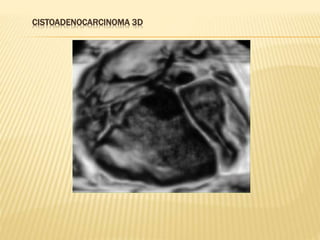

CISTOADENOCARCINOMA 3D

CISTOADENOCARCINOMA DE OVARIO

NEOPLASIA MALIGNA DE OVARIO

 CARACTERISTICAS ECOGRAFICAS

GENERALES

 Masas sólidas o quística con componente sólido

 Capsula con perdida de la continuidad

 Frecuentemente bilaterales

 Imágenes endo o exofiticas

 Tabiques con vasularización

 Flujo doppler con baja resistencia

 Ascitis